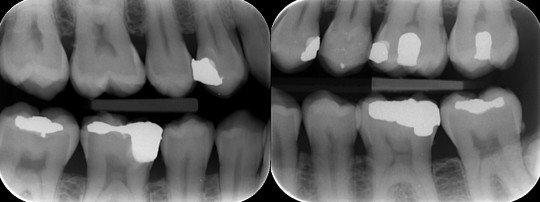

Bite wing neboli interproximální projekce slouží k získávání snímků, které lze nazvat jako snímky preventivní. Zhotovují se v časovém intervalu 6–24 měsíců, záleží na úrovni ústní hygieny pacienta, kazivosti chrupu a věku pacienta. Ke zhotovení těchto snímků používáme speciální držák s nákusným křidélkem, který pacient skousne mezi zuby v oblasti premolárů a molárů. Během vyšetření má pacient ústa zavřená.

Bite wing je skusový snímek zobrazující současně korunky všech laterálních zubů jedné strany čelisti i s přilehlou alveolární kostí. Jeho hlavní význam spočívá v časné diagnostice primárních či sekundárních kazů v mezizubním prostoru distálních zubů a v diagnostice recidivujících kazů. Dále je možné na rentgenovém snímku vidět přítomnost převislých výplní, okraje fixních protetických prací, zubního kamene a resorpci laminy corticalis při parodontitidě.

Pro kompletní vyšetření všech korunek laterálních zubů jsou nutné pouze 2 snímky. Toto vyšetření je velmi efektivní z důvodu malé časové náročnosti a nízké radiační zátěže.

Obr. 19. Bite wing (skusový snímek)